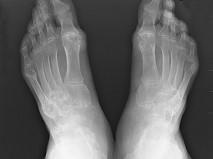

问题 男,72岁,手足多个小关节红肿热痛,并压痛明显,化验:白细胞升高,血沉增快,血尿酸升高,请结合所提供图像,选择最佳选项 ( )

选项 A、假痛风 B、滑膜炎 C、退行性骨关节病 D、痛风性关节炎 E、类风湿关节炎

答案 D